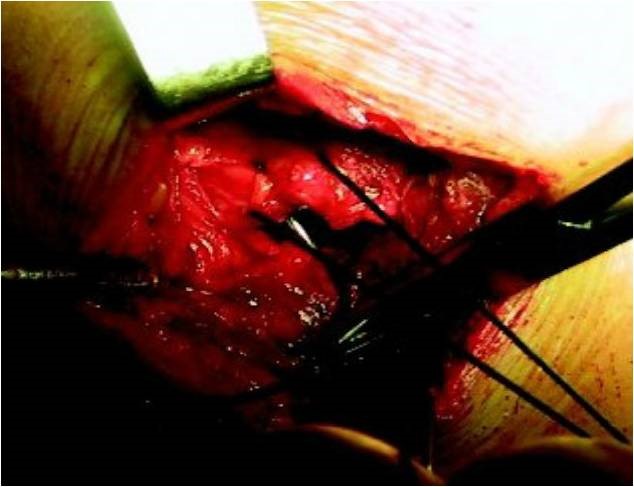

1.传统切开手术

早期的肩袖修复手术多采用切开的方式,这种手术方式必须先将肩峰外侧端或前侧端甚至全肩峰进行切除后才能进行肩袖修复术。尽管这种手术方式能明显缓解疼痛,但术后三角肌的力量会明显减弱,影响我们正常的肩关节功能。

但在关节镜技术诞生前,这一技术就是当时治疗肩袖撕裂的标准技术。

传统切开手术具有创伤大、恢复慢、无法发现和处理关节内病变等缺点。

传统开放切开手术 图片来源于网络,侵删